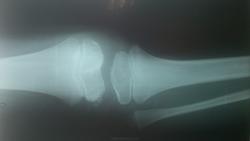

Мальчик 11 лет, жалобы на боли в коленных суставах в утреннее время. Движения в полном объеме, безболезненные, варусная деформация голеней с обеих сторон. У отца и деда выраженый гоноартроз.

Вопрос к детским рентгенологам (сама с детьми не работаю)-"лохматость" контуров суставных поверхностей бедренных костей у деток должна быть? А потом мне какие дополнительные тени кажутся, как суставные мыши у взрослых.

Костная структура соответствует возрастной норме. Единственное, что настораживает, великоват диастаз в межберцовом сочленинии. Я бы выполнила сравнительную рентгенографию обоих коленных суставов в прямой проекции с очень небольшой внутренней ротацией голеней 1 лучом на 1 пленке (с обязательным строгим соблюдением симметрии в укладке).

Костный возраст не соответствует 11 годам, по Садофьевой:

Полное окостенение эпифизов бедренной, большеберцовой и малоберцовой костей завершается несколько раньше (примерно в 8 лет)

Головки малоберцовок - как-то высоковато стоят по прямым снимкам, то ли укладка такая.

Вот-вот, и я об этом же. Дополнительные тени и нечеткость контуров.

Согласна, суставы не соответствуют возрасту, дополнительные тени - это добавочные ядра окостенения. Малоберцовые кости какие то длинные, щели межберцовых суставов широкие (в норме малоберцовая кость накладывается на большеберцовую). Вообщем, какие то диспластичные суставы. Костно-травматических изменений нет.

Мне периостальная реакция мерещится.

подозрение здесь на 2сторонний рассекающий остеохондрит ,ко-ый может иметь место в 30% случаев .слева в проекции дистального эпифиза бедра ,в проекции латерального мышелка бедра ,определяются точки окостенения ,один из находится на большом удалении от мышелка,чего не должно быть ,вероятнее всего яв-ся костным фрагментом.справа четко определятся костный фрагмент вогнутой формы (ядро окостенения всегда должно быть в этой зоне округлой формы ),с нечеткостью замыкательной пластинки (размытость).решить вопрос может мрт-будет отек и гипоинтенсивный сигнал во всех последовательностях(участок некроза)

Всё то, что Валентин Львович отметил стрелочками - не норма. Я бы описал на месте автора побробно снимок без заключения, а остальное предоставил ортопеду. У нас так и делается. И это правильно.